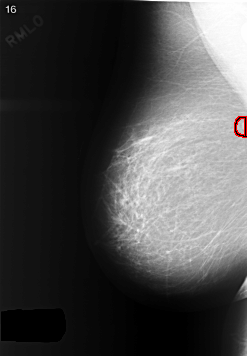

C_0364_1.RIGHT_MLO

FILE: C_0364_1.RIGHT_MLO.OVERLAY

TOTAL_ABNORMALITIES 1

ABNORMALITY 1

LESION_TYPE MASS SHAPE ROUND MARGINS CIRCUMSCRIBED

ASSESSMENT 3

SUBTLETY 5

PATHOLOGY BENIGN

TOTAL_OUTLINES 1

BOUNDARY